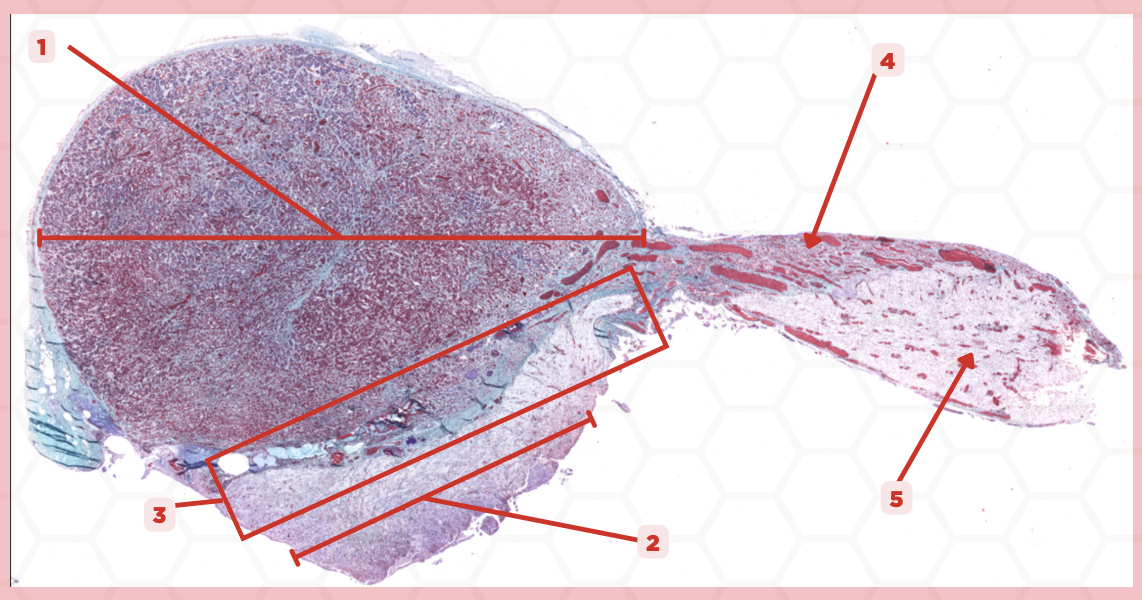

Pituitary

Identify the specimen.

Anterior Lobe

Identify the structure labeled as 1.

Posterior Lobe

Identify the structure labeled as 2.

Intermediate Lobe

Identify the structure labeled as 3.

Pars Tuberalis

Identify the structure labeled as 4.

Pituitary Stalk

Identify the structure labeled as 5.